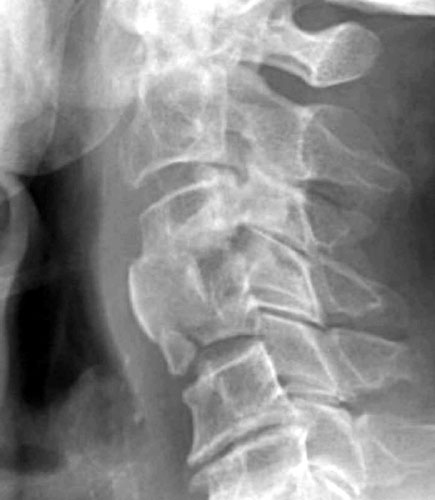

Endplate Fracture

This radiograph take 1 month later demonstrates anterior

extrusion of bone graft material at C3-4 and an endplate fracture at C4. |